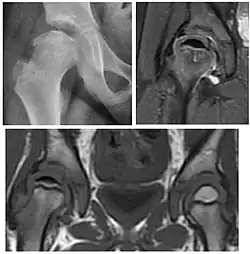

Figure 7:

-

Axial CT image of pigmented villonodular synovitis eroding the posterior cortex of the femoral neck.[1] -

Sagittal T2* gradient echo image showing a posterior soft tissue mass with hypointense areas secondary to hemosiderin deposition.[1] -

X-ray of synovial chondromatosis.[1] -

CT of synovial chondromatosis.[1]

In synovial proliferative disorders, MRI demonstrates synovial hypertrophy. In the case of PVNS, characteristic foci of low signal intensity related to hemosiderin deposition are better seen on gradient echo T2* images (Figure 7). In the case of synovial osteochondromatosis, the synovial hypertrophy is accompanied by intermediate signal cartilaginous loose bodies and/or low signal calcified loose bodies.[1]